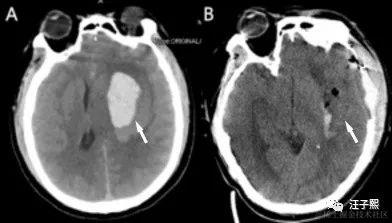

我见没有达到目的,换了一个角度继续问,“Z医生,从我前天拍的核磁共振检查报告来看,明天的手术,切除肿瘤难度大吗? ” 出乎我意料,这次Z医生没有给出诸如“有一定的难度”这样的答复,而是给我讲述了一些常识。放射科出具的核磁共振检查报告结果,就是病人拿给外科大夫看的那一张张黑乎乎的塑料片子,到底是怎么生成的呢?这要从我们是如何进行核磁共振检查说起。

参加核磁共振检查的人,会平躺在一个装置上(有点像电影《普罗米修斯》里女主伊丽莎白-肖博士进行剖腹手术,取出自己体内异形使用的手术仓),这套装置会产生一个特殊的磁场,并发出无线电射频脉冲激发人体内的氢原子核,引起氢原子核共振,并吸收能量。在停止射频脉冲后,氢原子核按特定频率发出射电信号,并将吸收的能量释放出来,被检查装置的接受器收录,通过计算机处理生成图像,这就是做核磁共振成像的一个完整流程。

Z医生告诉我,“你三天前的核磁共振片子结果,仅仅是你当时颅内的一个二维投影,我们可以用来作为参考进行手术难度评估,但它不是评估手术难度的决定性依据。一切都只能到了手术中,进入颅内看到实时情况,才能准确下结论。 ” 我心想,嗯嗯,我明白,核磁共振其实就是颅内实时状态,在某个时间点上给它做的一个镜像(snapshot), 这个镜像把颅内状况从3维降成了2维,根据该镜像无法逆向还原制作镜像那个时间点内的颅内状况。